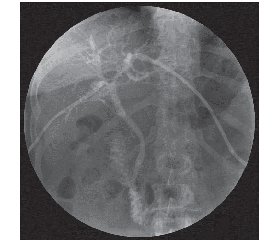

За период с 2011 по 2016 год в клинике ГУ «ИОНХ им. В.Т. Зайцева НАМНУ» обследовано и пролечено 45 больных с холангиокарциномой, осложненной механической желтухой. Возраст больных составил от 34 до 79 лет, мужчин было 19 (42,3 %), женщин — 26 (57,7 %). Уровень билирубина при поступлении — от 182 до 398 ммоль/л (средний — 312,4 ± 38,1 ммоль/л). Всем больным проводили общеклинические, лабораторные (уровень опухолевых маркеров СА-19-9) и инструментальные методы исследования (магнитно-резонансная или спиральная компьютерная томография с внутривенным контрастированием, холангиография), использование которых позволило выявить характер поражения и его распространенность, особенности артериальной, портальной и билиарной анатомии, признаки опухолевой инвазии в сосуды гепатодуоденальной связки. Всем больным выполнялось чрес–кожное чреспеченочное холангиодренирование (ЧЧХД) как первый этап лечения. Следует отметить, что целью первого этапа лечения данной группы больных является не только декомпрессия желчных путей, но и профилактика возморисжных осложнений, в частности полиорганной недостаточности. Исходя из резектабельности опухоли, возраста больных и сопутствующей патологии все больные были разделены на 3 группы. В первую группу во–шли 23 больных, которым выполнялось ЧЧХД (рис. 1) либо ЧЧХД + стентирование как окончательный этап паллиативного лечения. В дальнейшем этим больным проводилась системная полихимиотерапия. Во вторую группу вошли 9 пациентов, которым выполнялось ЧЧХД в сочетании с внутриартериальной химиоэмболизацией (ВАХЭ) (рис. 2). Третью группу составили 13 больных, которым проводилось ЧЧХД в сочетании с радикальной операцией. Радикальные операции выполнялись через 2–3 недели после предварительной декомпрессии желчных протоков, купирования явлений холангита и печеночной недостаточности, когда отмечалась тенденция к нормализации биохимических показателей, стабилизации общего состояния больного.